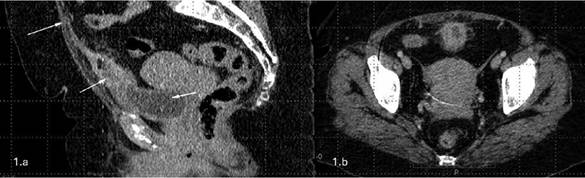

Durante la hospitalización por la infección aguda y el antecedente de recurrencia y resistencia se solicitó una urotomografia, para descartar etiología anatómica o otro foco de infección, en la cual se evidencia divertículo uracal con paredes engrosadas, con reforzamiento tras medio de contraste, presencia de aire en su interior, además de estriación de la grasa adyacente (Fig 1-3).

A la izquierda Fig 1a: TAC sagital, 1b TAC axial: ambas realizadas en fase venosa: la flecha azul muestra el ligamento umbilical, mismo que se encuentra cerrado; la flecha naranja muestra el realce y marcado engrosamiento irregular de las paredes del divertículo uracal, en su interior presencia de escaso liquido; la flecha amarilla la vejiga con escaso contenido hipodenso

FIGURA 1: